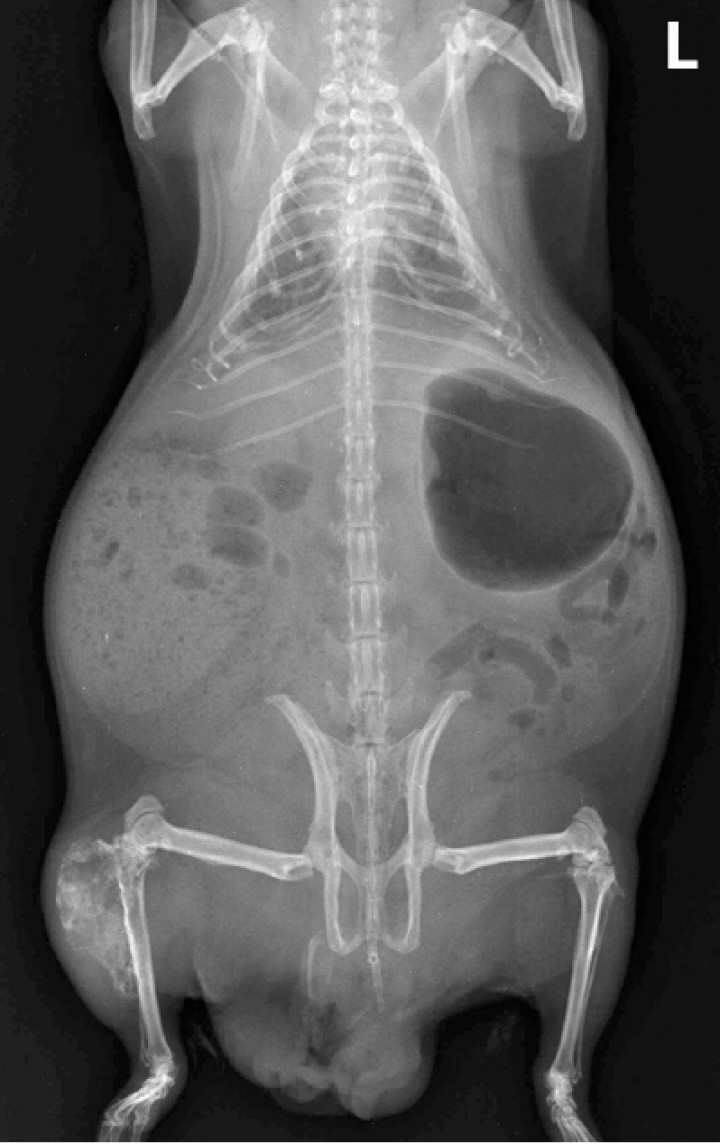

Las localizaciones de los condrosarcomas eran tibia y/o peroné (2 casos, ambos en su epífisis proximal y extendiéndose hasta la diáfisis) (Fig. 1), pelvis (1 caso), escápula (1 caso), dorso del cráneo (1 caso; Fig. 2) y en las últimas dos vértebras lumbares (1 caso). Una cobaya mostró múltiples masas óseas distribuidas desde la tibia/peroné hasta la zona lumbar caudal o coxal (Fig. 3), aunque la masa primaria involucraba aparentemente la epífisis proximal de la tibia y peroné, y alguna de las otras masas se interpretaron como posibles metástasis en ganglios regionales (lumbosacro, inguinal y/o poplíteo). Clínicamente, los animales presentaron anorexia o hiporexia (2 casos), apatía (1 caso), pérdida de peso (1 caso) y signos clínicos relacionados directamente con la localización de la neoplasia, como claudicación, ataxia, pérdida de propiocepción, disuria y dolor regional (cada uno de estos síntomas en una única cobaya). En una cobaya con metástasis pulmonares se observó disnea. En 4 cobayas se disponía de estudios radiológicos, que demostraban masas moderada o intensamente radiopacas (opacidad mineral) (salvo en la cobaya 6 [Fig. 1]), las cuales se originaban en las corticales primarias con invasión y osteolisis variable del hueso esponjoso (Figs. 1, 2B y 3). En 2 cobayas se apreciaron numerosos nódulos pulmonares de pequeño tamaño y opacidad similar a las masas óseas (Fig. 3). Una de estas cobayas (caso 1) mostraba además un nódulo similar en la zona inguinal, interpretado como una posible metástasis en ganglio regional (Tabla 1).

<p>Cobaya 4. Imagen radiológica de un condrosarcoma avanzado con múltiples masas desde la tibia/peroné (presumible masa primaria) hasta el coxal o zona lumbar caudal, así como metástasis numerosas en ambos pulmones. L: izquierda.</p>

Figura 3

Cobaya 4. Imagen radiológica de un condrosarcoma avanzado con múltiples masas desde la tibia/peroné (presumible masa primaria) hasta el coxal o zona lumbar caudal, así como metástasis numerosas en ambos pulmones. L: izquierda.